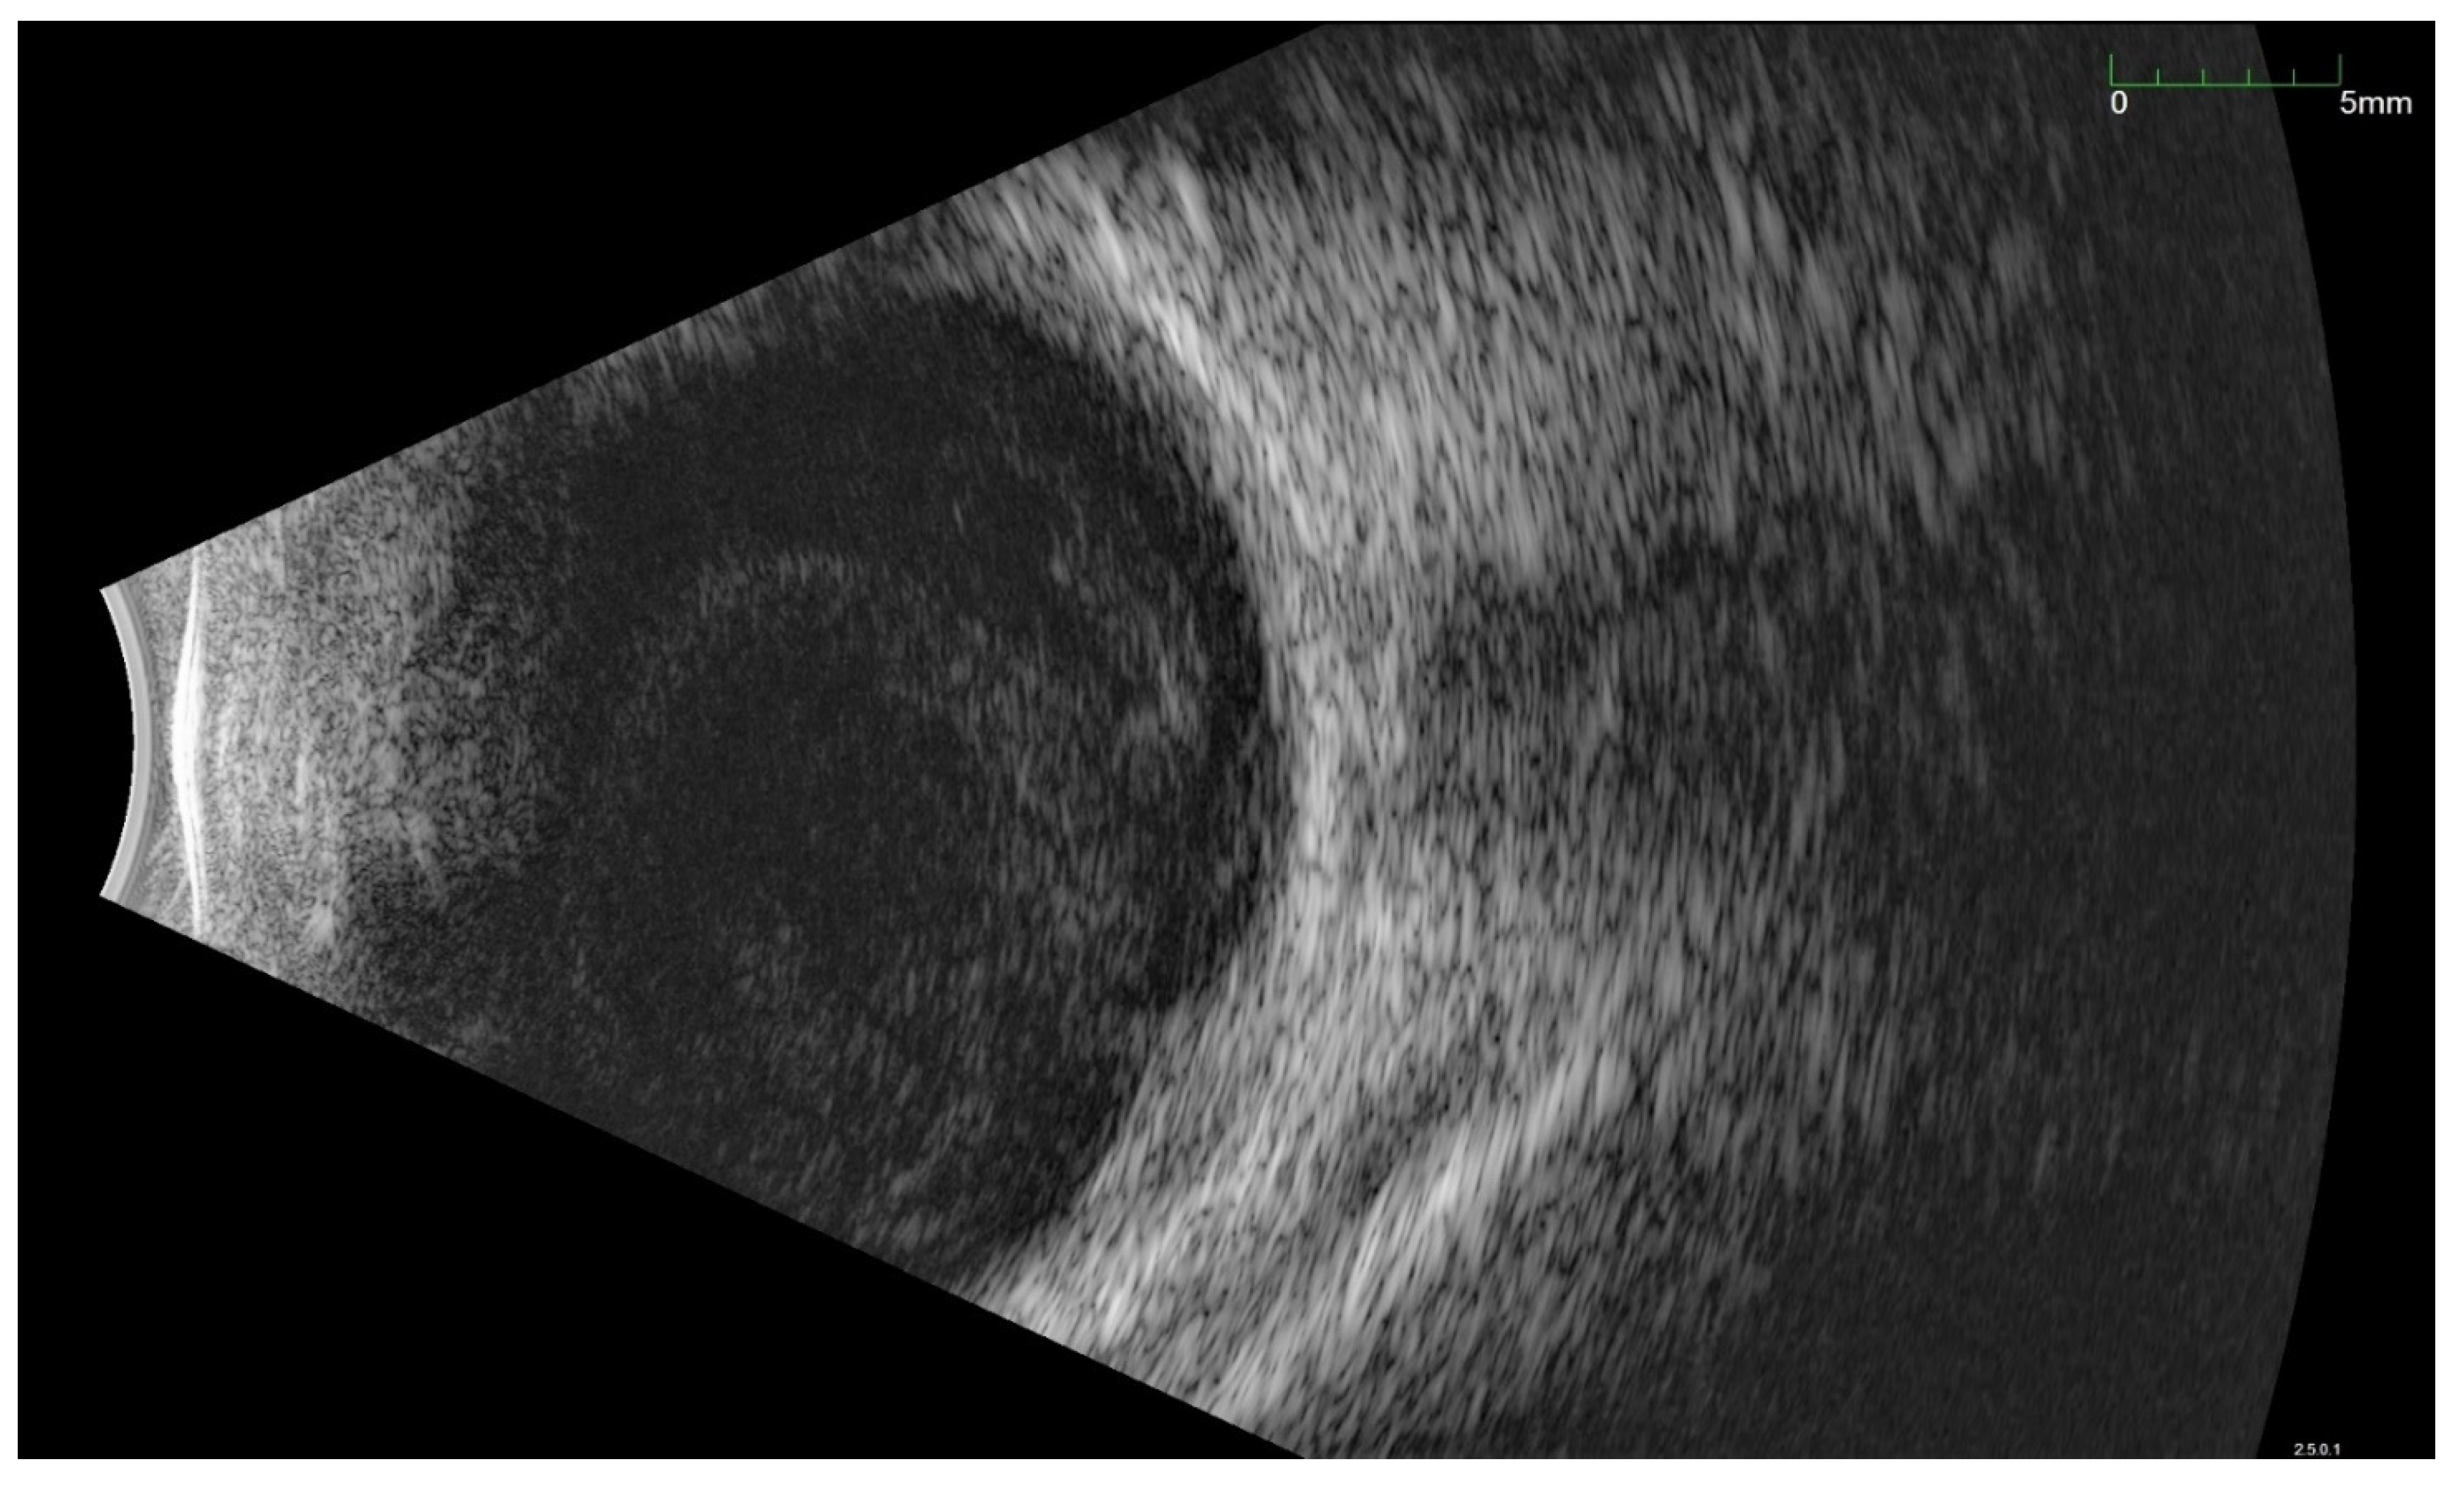

All of the above circumstances make the assessment of the vitreous body and retina in an ophthalmoscopic examination often impossible. The basic diagnostic tool in such cases is an ultrasound examination. Vitritis is inherent part of EE. Ultrasonography is nonspecific, however, it can indicate severity of the posterior involvement (Figure 6 and Figure 7) [80]. It also allows the assessment of the progression of changes (Figure 8). Features characteristic for EE include strands and membranes with reduced mobility (Figure 9). Other common changes are retinal detachment and subretinal abscess (Figure 10).

Figure 6.

Ultrasound B scan with a hyperechoic exudate filling almost the entire vitreous chamber. Advanced inflammation in a patient with bacterial EE.

Figure 7.

Ultrasonography B scan with bacterial EE. As in Figure 6, hyperechoic densities fill the entire vitreous chamber. However, the lower intensity of the changes is noticeable.